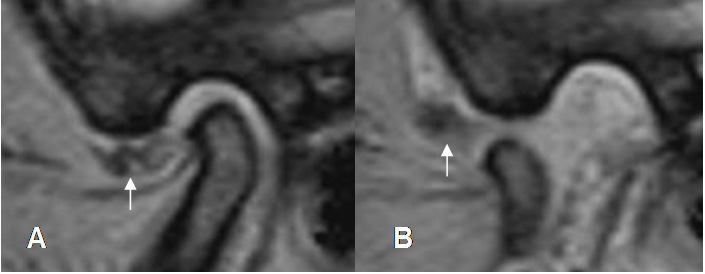

Fig 10. Angulo del Menisco.

A: RM Secuencia GE sagital con ángulo normal.

B: RM Secuencia GE sagital, con disco desplazado anteriormente y un ángulo mayor de 30º.